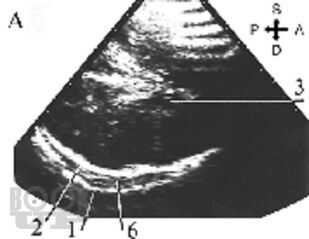

Учебное пособие содержит материал по анатомо-физиологическим особенностям новорожденных, биомеханике родовых повреждений головы и клинической картине родовых травм. Приведены инструментальные методы оценки функционального состояния головного мозга и принципы консервативного и хирургического лечения детей с родовой травмой, а также клинические примеры, тестовые задания и ситуационные задачи.